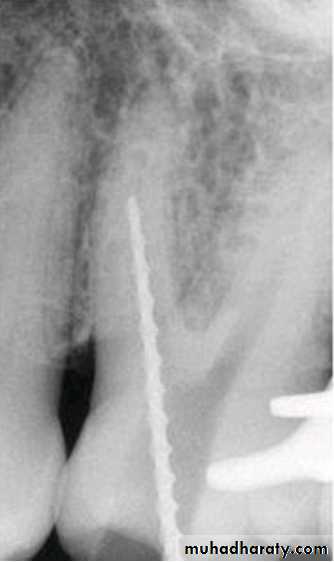

When a curved foramen is filed with pressure against the outer side of the curvature.

Repeated filing Zips and transport the foramen.

zipping